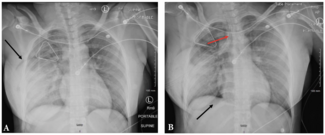

A 31-year-old woman who recently had a breast augmentation presented after sustaining a gunshot wound to the right chest.